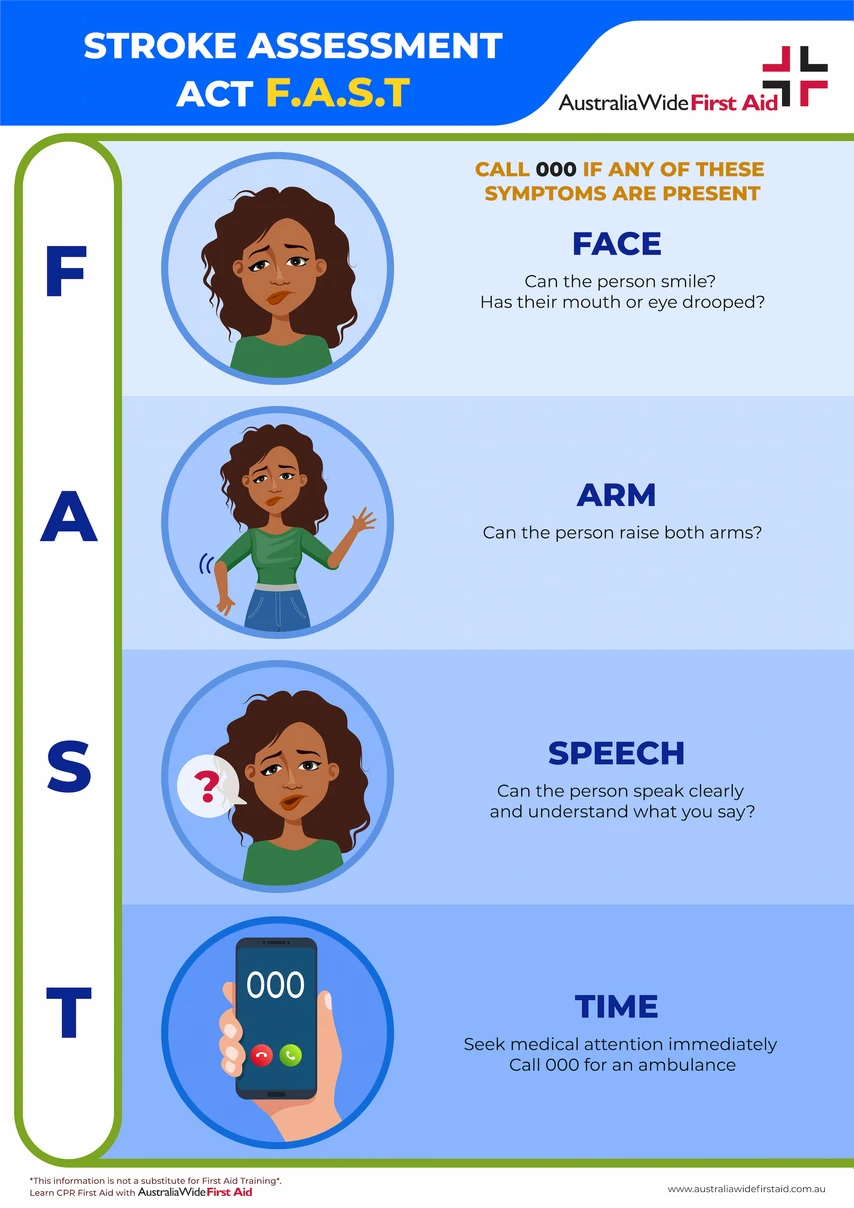

If a person shows even one sign in the F.A.S.T. test below, call Triple Zero (000) straight away.

Prompt action can prevent further damage to the brain and help the casualty make a full recovery. Delay in getting treatment can result in death or major long-term disabilities.

The Stroke Foundation recommends using the F.A.S.T test to remember the main symptoms of stroke.

As cited by the American Stroke Association, the acronym F.A.S.T represents:

You should also call 000 even if someone fails the F.A.S.T test but does not experience any pain, as strokes do not hurt for many people.